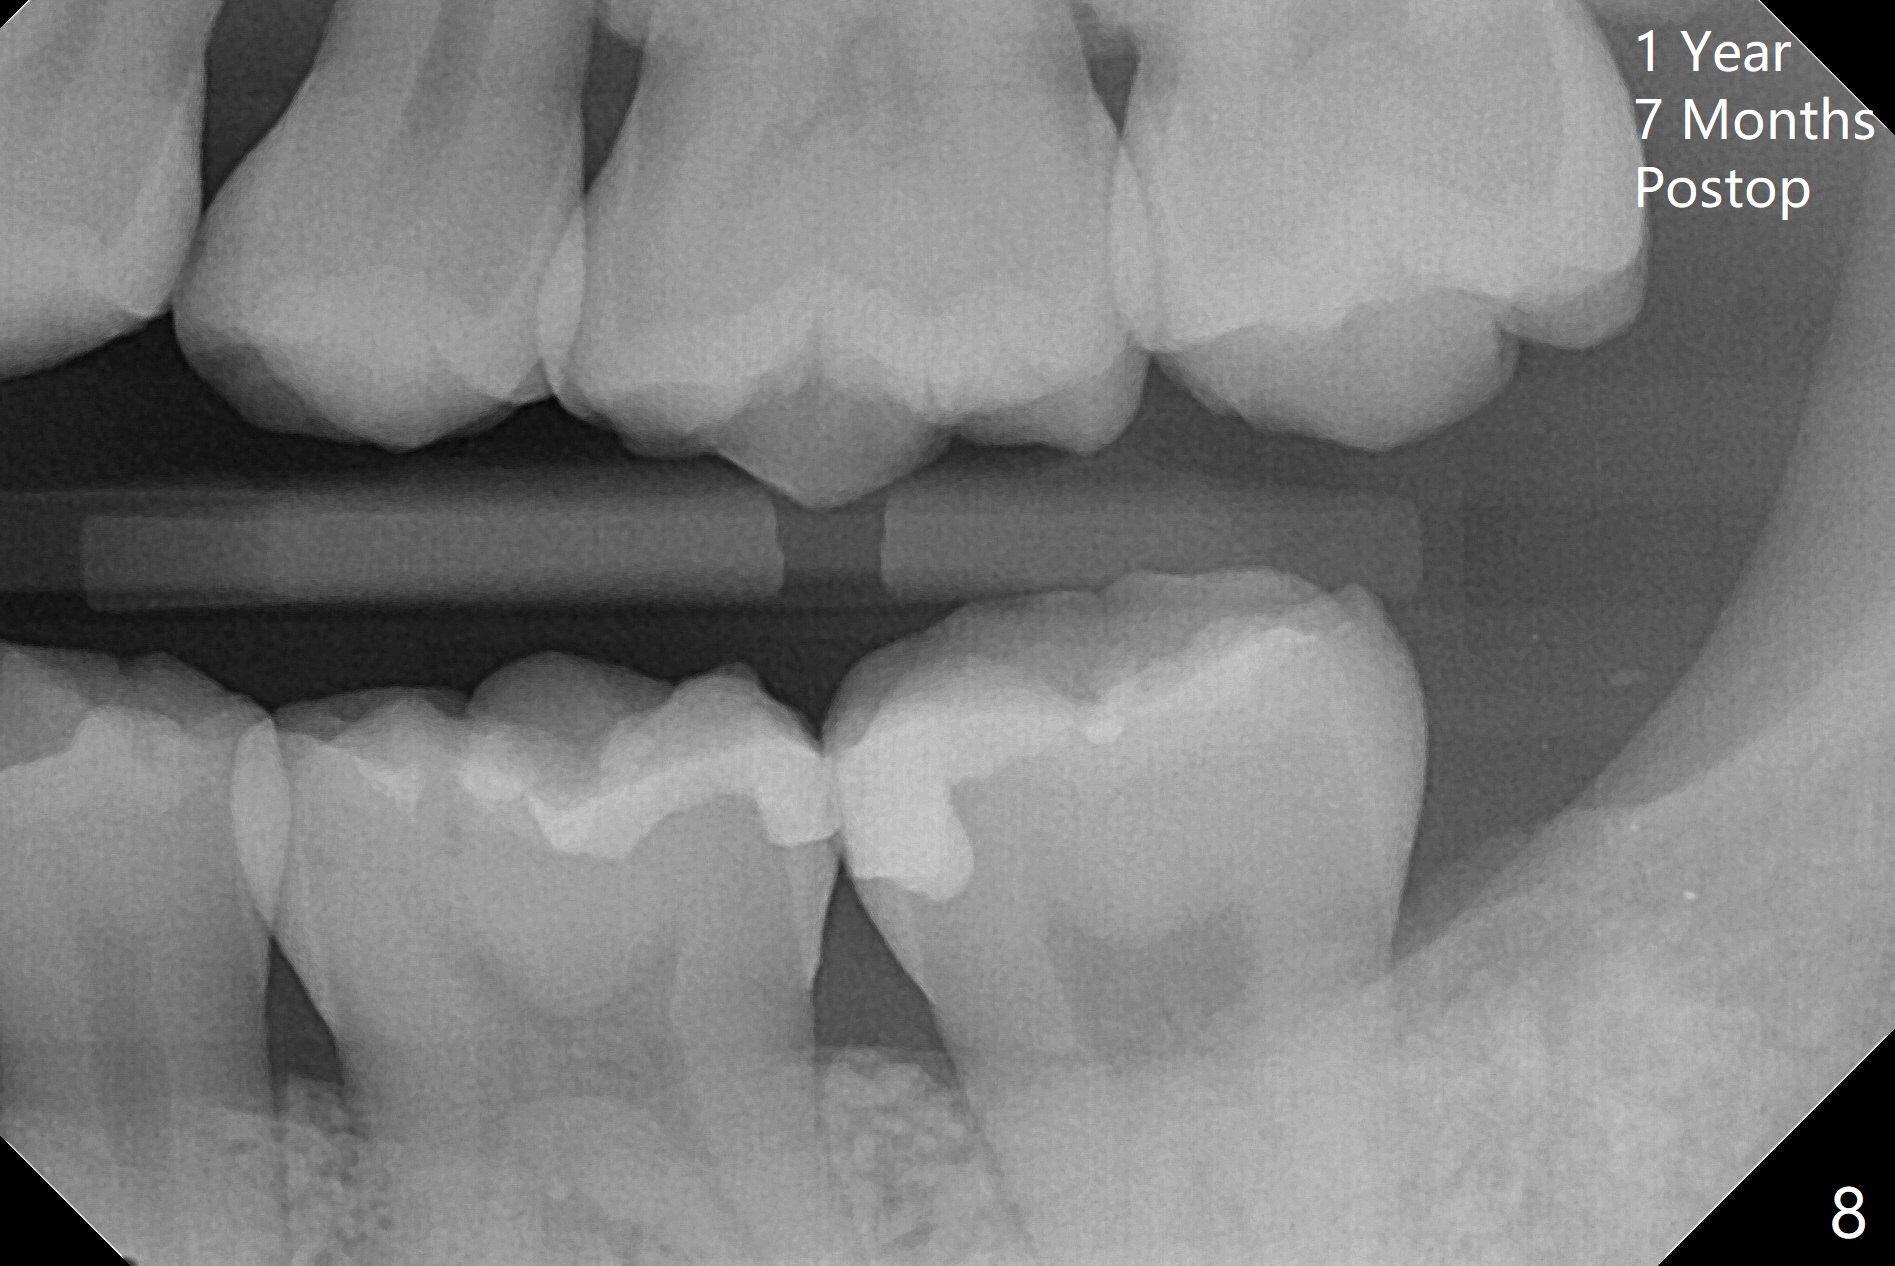

A 27-year-old woman (nervous) is going to return for #16 and 17 extraction (Fig.1). Offer sedative (Valium) if she cannot overcome fear. Take PAs for #17 and 32 to confirm Buccal Impaction, which dictates position of the accessory incision to reduce loss of bone graft in case of wound dehiscence. Place Collagen Plug (1/2 piece) in the apical portion of the sockets of the lower 3rd molars, while Augma and Osteogen Plug (1 piece) in the coronal half of #17 and 32, respectively. Place additional Collagen Plug for the remaining socket if needed before 4-0 PGA suturing as the 2nd step to decrease the chance of losing bone cement. Preop PA shows that the tooth #17 seems to be mesial (Fig.2 arrow). The accessory incision is placed mesiobuccal of the tooth #18 (Fig.4 red oblique line, Fig.6) so that it is not overlying the bony defect (Fig.4 arrowheads). Since the access to the impacted tooth is limited, small field of CT is taken (Fig.3,4), which shows the root is yet to be exposed (Fig.3 R). After tooth removal, Collagen plug is placed in the apex of the socket for hemostasis (Fig.5 C), while Bond Apatite coronal for bone regrowth (A). There is no dehiscence 11 days postop (Fig.7), although the patient complains of pain in the jaw and the temporomandibular region. The anterior portion of the external oblique ridge forms 1 year 7 months postop (Fig.8).